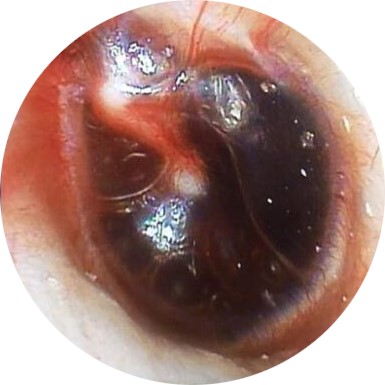

| LEVEL | DESCRIPTION | PICTURE |

| TEED 0 | Normal tympanic membrane. No evidence of injury despite the presence of symptoms. |

|

| TEED 4 | Dark and slightly bulging tympanic membrane due to free blood in the middle ear (a fluid level may also be present). |